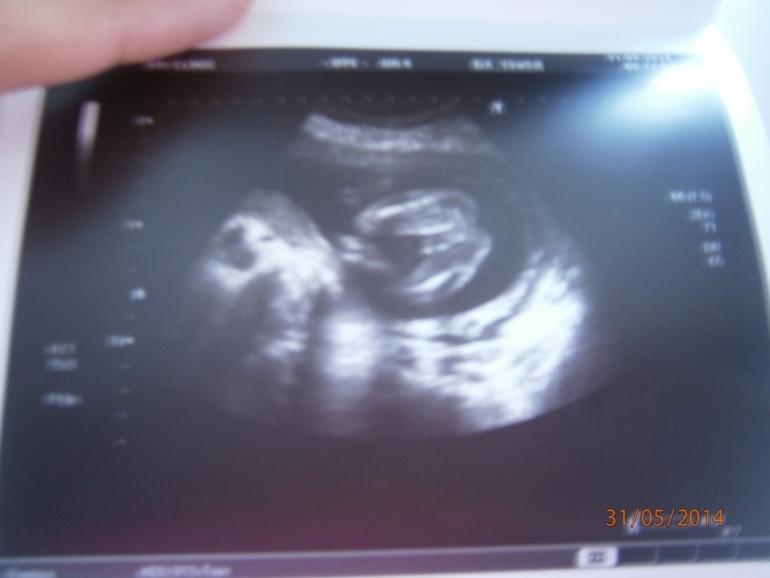

. Я вам реально говорю ...Я больно не отреагировала, так как для меня было важнее все показатели...Дальше мы замерли и стали смотреть на экран и слушать узистку. Я не дышала, очень переживала. Моя малютка сразу начала пинаться. Все показатели в норме. Но в конце врач так долго стала смотреть наше сердечко, вертела меня то на один бок, то на другой. Мне стало страшно. Она объяснила это тем, что Срок у меня 19-20 нед, обычно сердечко смотрят в 22-24 нед, поэтомудля такого осмотра рановато, но она должна все с точностью рассмотреть. В итоге, по показаниям все хорошо - 21-22 неделям параметры соответствуют, но напугала она меня сильно. Но назначила пройти в 22-24 нед Д-ЭХОкг. Девочки, правду она мне сказала, что еще не очень видно? У кого так было?! Я напугана.

. По фото можете убедиться сами. Значит будем растить мужиков...Но, конечно, по посл постам наших девочек, мне еще хочется верить, что там сидит девочка). Стыдно перед сыночком стало...так, конечно, нельзя...Муж стал как бы издеваться, смеялся надо мной, а собой горд, что у него 2 сына. Да какая им то разница...мы воспитываем...мальчиков из семьи заберут жены, а дочка всегда будет ближе) В общем, я собралась и начали думать над именем, т.к. имя у нас было заготовлено только для доченьки. Теперь все в раздумьях...

Фото не очень качество( Но все самое главное, думаю, видно.